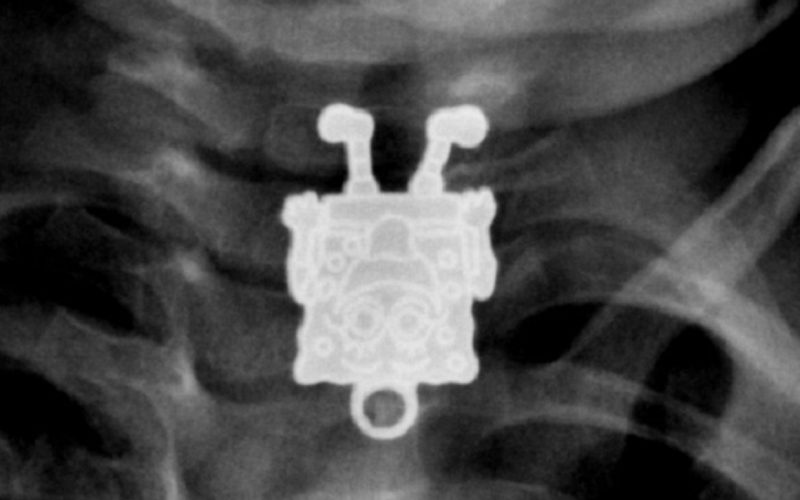

Sünger Bob

Kontrole gelen 16 aylık bir bebeği kontrol eden doktorlar, röntgende Sünger Bob Kare Pantolon’u görünce çok şaşırmışlar. Sonradan anlaşıldığına göre bebek, kız kardeşinin Sünger Bob şeklindeki kolye ucunu yutmuş. Doktorlar, nesneyi hiçbir sorunla karşılaşmadan çıkartmayı başarmışlar.